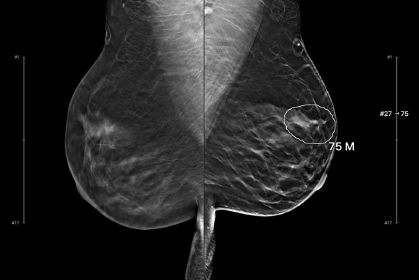

DBT received U.S. Food and Drug Administration (FDA) clearance in 2011, but many insurers didn’t immediately adopt full coverage of the procedure without patient cost sharing. A $45 out-of-pocket fee had initially been charged at the group’s academic institution and affiliated outpatient imaging centers, but was refunded after insurance payment was received. After most insurers began covering DBT, this fee was eliminated in January 2021.

To assess the effect of out-of-pocket costs on the use of DBT vs. digital mammography for breast cancer screening across different patient groups, the researchers retrospectively analyzed screening mammograms conducted before (March 2018 to January 2021) and after (February 2021 to August 2022).